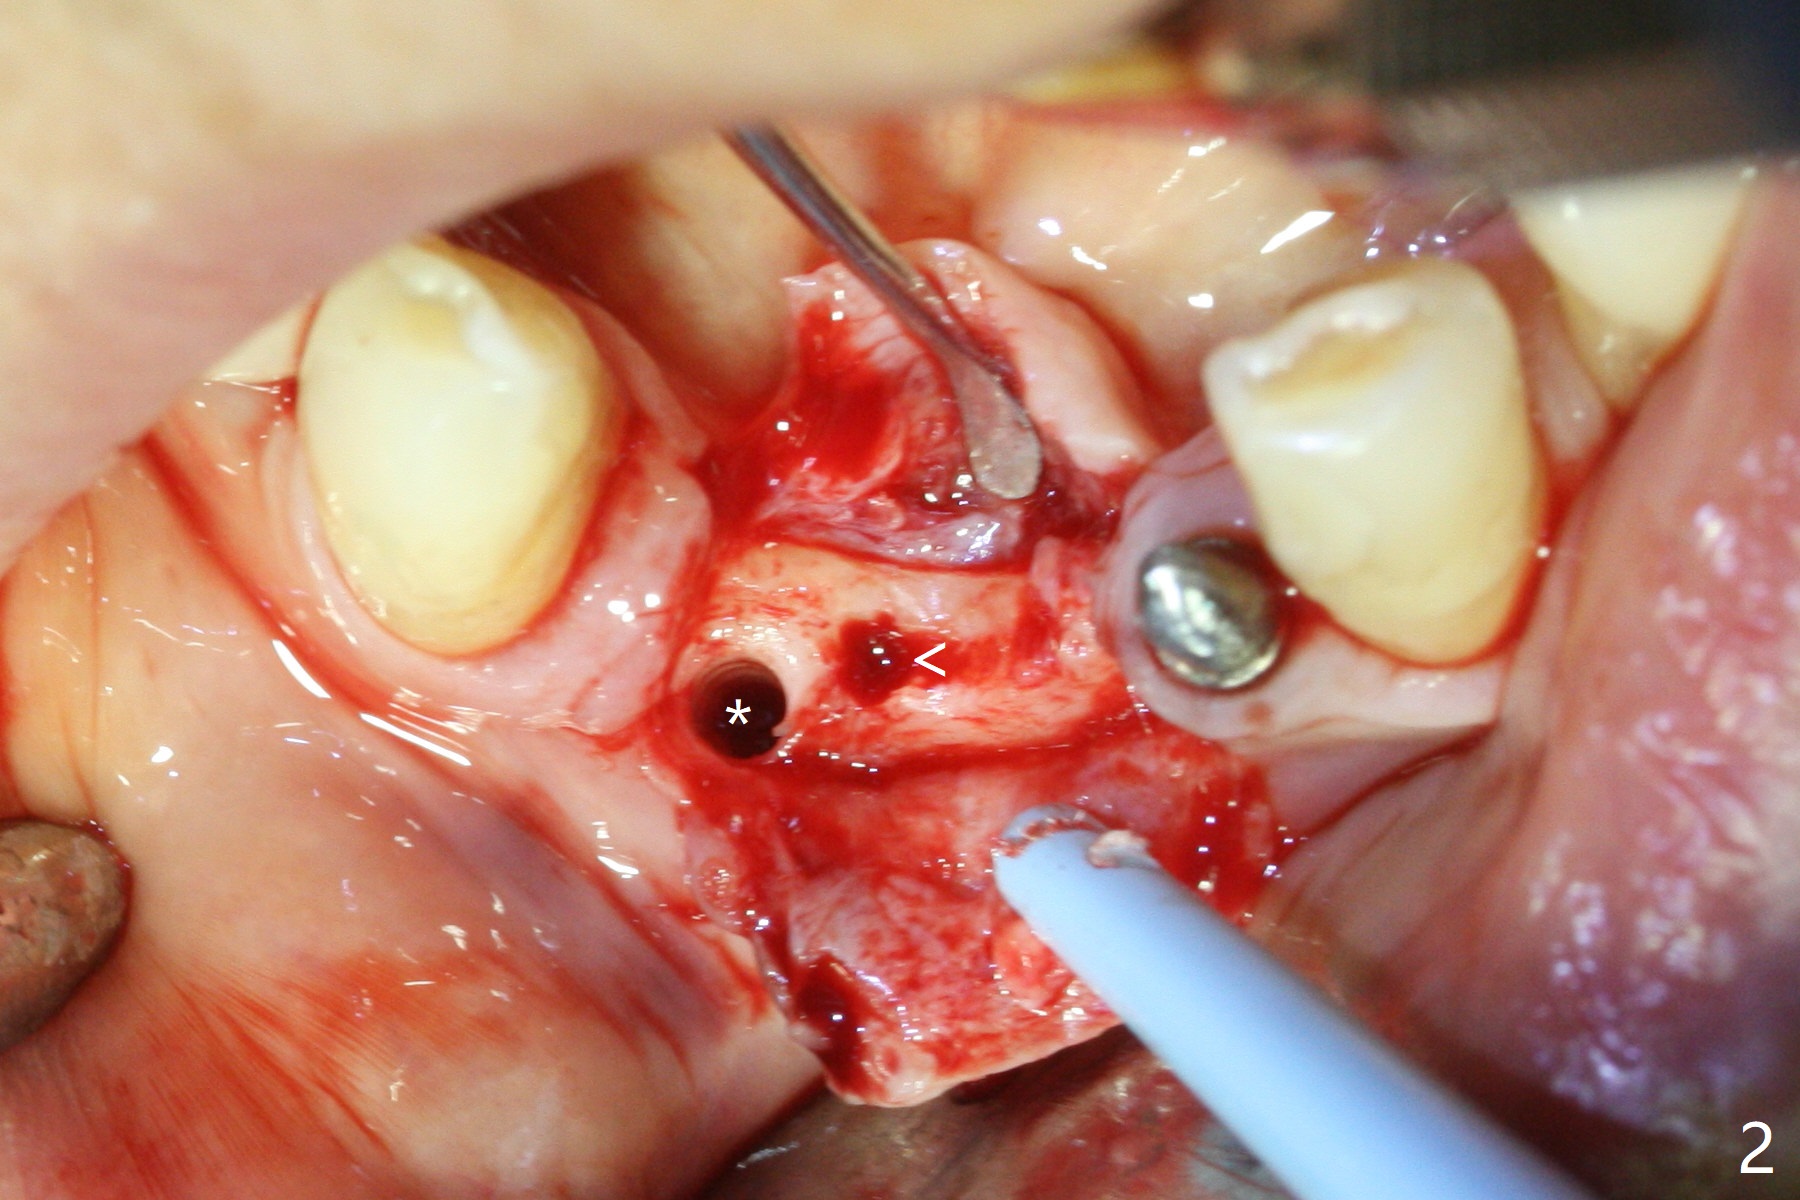

After removing #23-26 FPD and the 3x14 mm 1-piece implant at #26 (Fig.1,2 *), a new osteotomy is initiated in the narrow ridge (after ridge top reduction) approximately at #25 (Fig.2 <). Following placement a 2x10(4) mm implant at #25 (Fig.3-5) and Osteogen plug in the osteotomy at #26, Vanilla graft is placed around the implant, especially buccal. Periodontal dressing is applied after suturing. The buccal and lingual flaps are erythermatous and edematous without pain 8 days postop (Fig.6). The wound seems to be healing 2 weeks postop (Fig.7), no sign of osteonecrosis. With placement of a 2 mm implant at #25 (Fig.8 (>: bone graft buccally)), the buccal plate remains normal in thickness. When a 3 mm implant is placed at #23 (Fig.9), approximately 4 threads appear to be exposed (between arrowheads), partially due to the thick lingual plate (*).